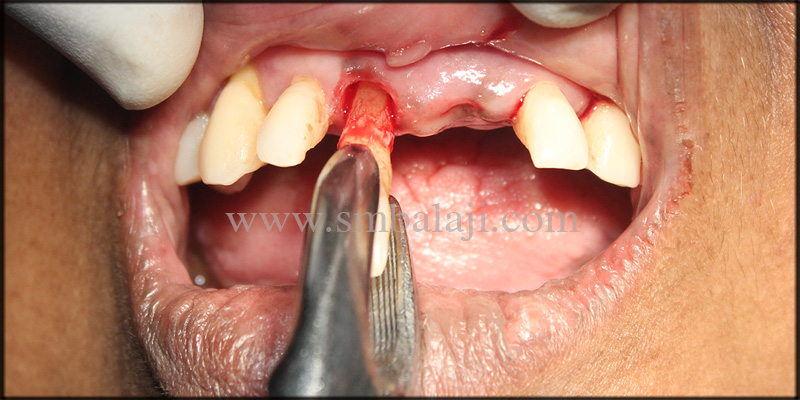

Under local anesthesia, Dr. SM Balaji extracted the mobile lower anterior teeth and removed the infected dental implant from the jaw bone. The recipient site was curetted and irrigated well with a sterile solution. Patient was put on antibiotics for a better healing process. A temporary removable prosthesis was given to replace her missing teeth.